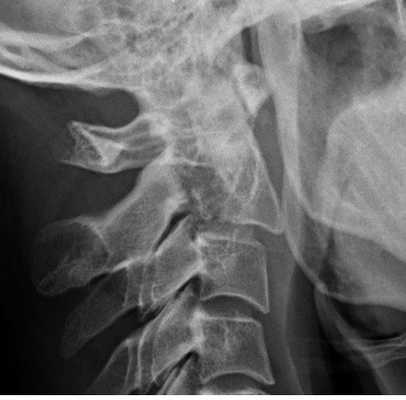

Перелом С2. Рентгенограмма в боковой проекции. Кольцо незамкнуто вследствие смещения зубовидного отростка назад.

Перелом С2 «повешенного». Рентгенограмма в боковой проекции. Смещение тела С2 вперед, отрыв задних элементов.

Обследование начинается со стандартной рентгенографии в 3 проекциях - боковой, передне-задней (прямой) и через рот.